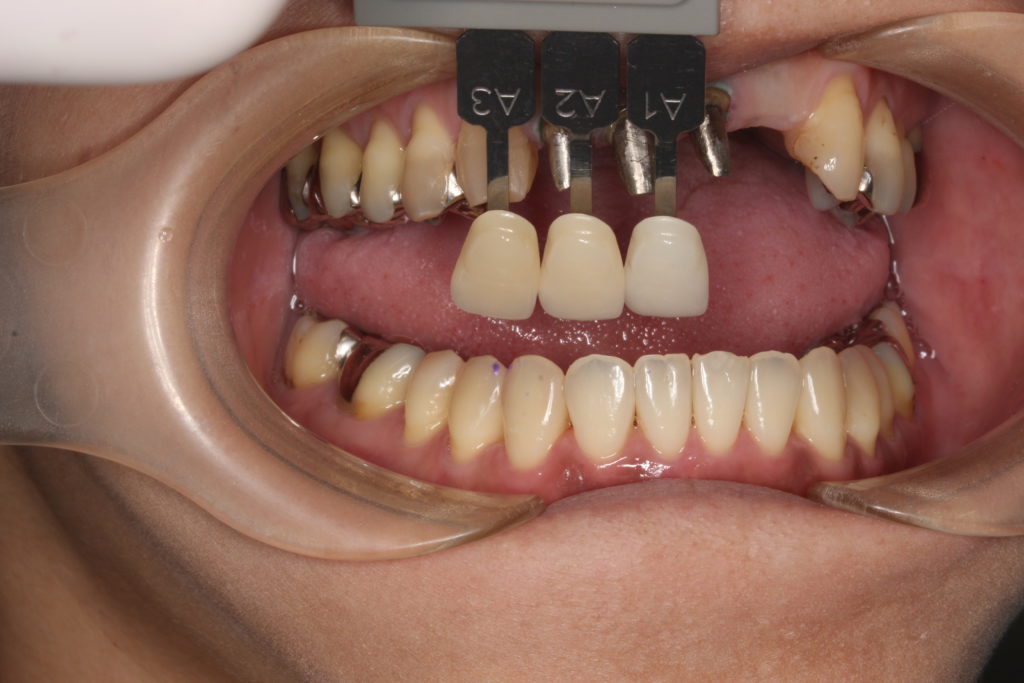

下の歯の色も参考にします。

お口の中、前歯の色味のバランスを考えて合わせていきます。

当院では自費専門の技工士がその方に合った歯を製作します。

材質はジルコニアセラミックを使い、綺麗に仕上げます。

下の歯の色に合わせて、白めに仕上げています。